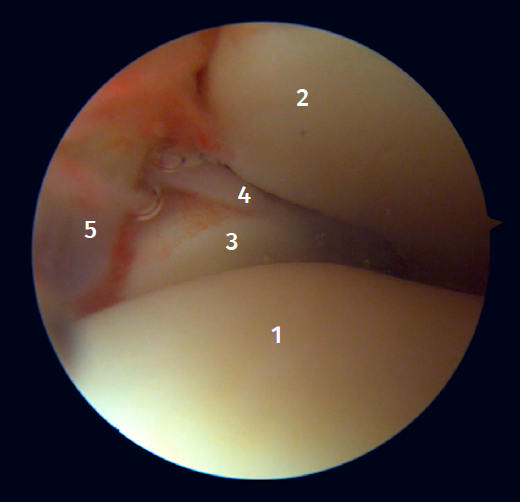

Posterior arthroscopic view

From the posterolateral approach we identify the lateral (fibular) malleolus and, from here, we visualize the intra-articular fibers of the PTFL, which run obliquely and insert into the distal portion of the tibia. We also see the distal thickening of the PTFL (transverse ligament) in continuity with the posterior lip of the distal tibia (Figure 4).

Arthroscopic anatomy of the medial complex

Arthroscopy allows us to see the deep fibers of the deltoid ligament, corresponding to the intra-articular portion of the ligament. Medial and proximal to the tip of the malleolus we have the insertion of the deep layer of the deltoid ligament. If there is no injury, we will see the anterior portion of the deep tibiotalar fibers. When injury is present, we can visualize the intermediate and posterior portion. The superficial bands, due to their more external location, are not visible by arthroscopy, unless there is no lesion of the deep bands (Figure 5).